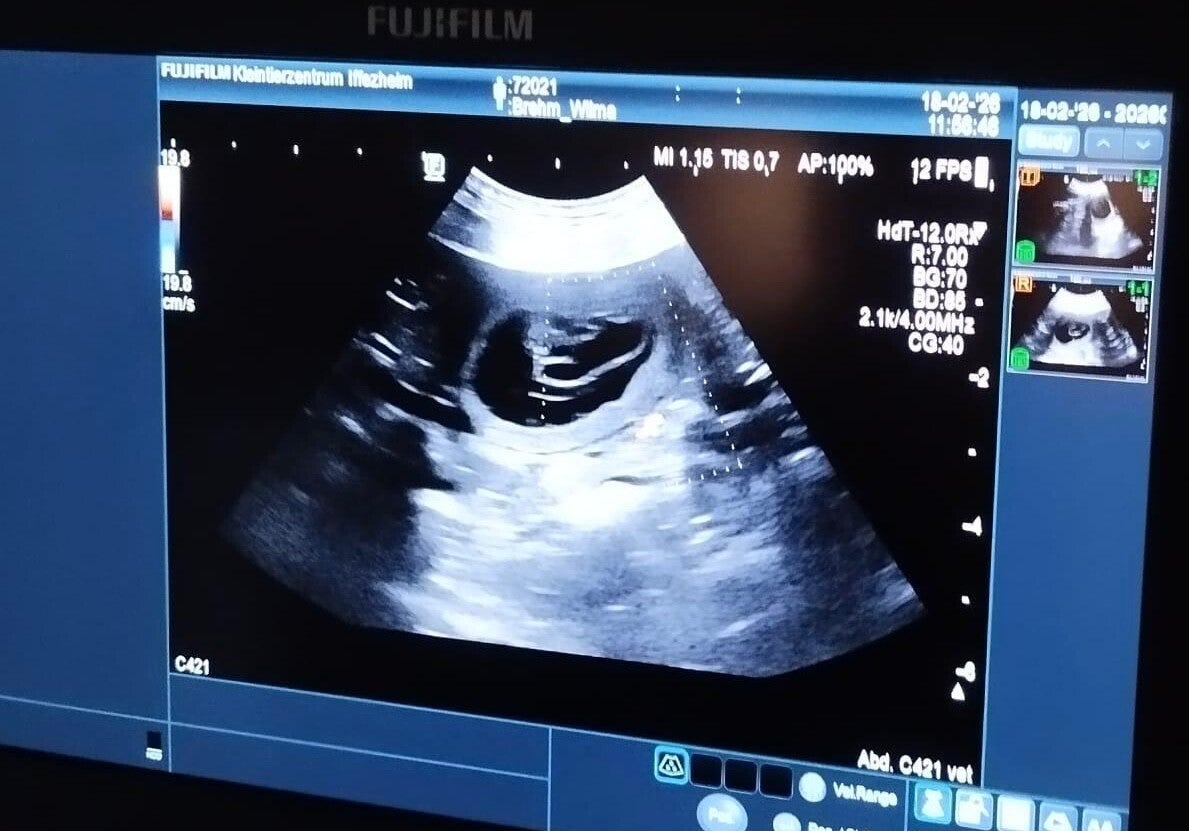

Wilma beim Ultraschall am 18.02.2026 -> Wilma ist trächtig

Brown Temptations Number One (Wilma) Loretta The Art of Slowing Down - Chuck